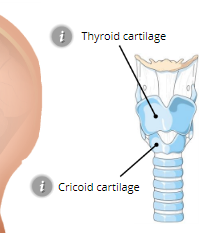

Larynx (voice box)

Thyroid Cartilage

Cricoid Cartilage